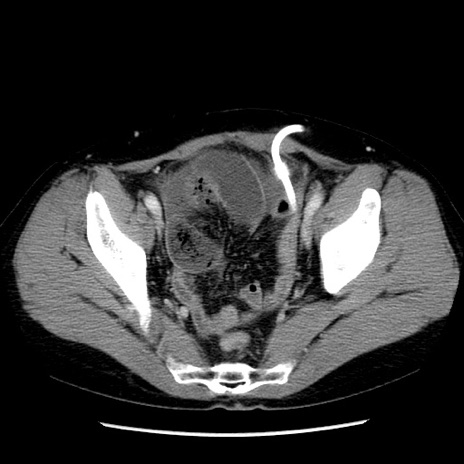

症例6(横断像)

【症例】50歳代女性

【主訴】下腹部痛

【現病歴】本日朝より下痢2回あり。 昼食を食べた後、嘔吐3回、下腹部痛認め、症状軽快せず、当院救急搬送。

最終食事:本日昼(生ものなし)。 昨日の夜、刺身を食ぺたとのこと。周囲に同様の症状の者なし。普段、排便は毎日あるとのこと。

【既往歴】卵巣癌術後(8年前に当院で卵巣摘出)

【身体所見】 意識清明、腹部:平坦、腸蠕動音→、やや硬、下腹部自発痛・圧痛あり、反跳痛あり、筋性防御なし。

【データ】WBC 16000、CRP 0.01